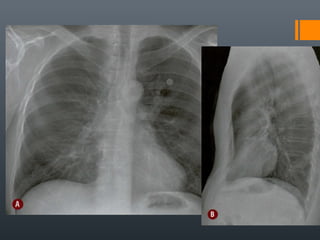

O documento discute vários conceitos radiológicos incluindo consolidação, atelectasia, nódulos, pseudocavidades e padrões intersticiais, fornecendo definições, sinais e diagnósticos diferenciais para cada tópico. Ele também discute a redução da atenuação pulmonar e fornece um link para mais informações.